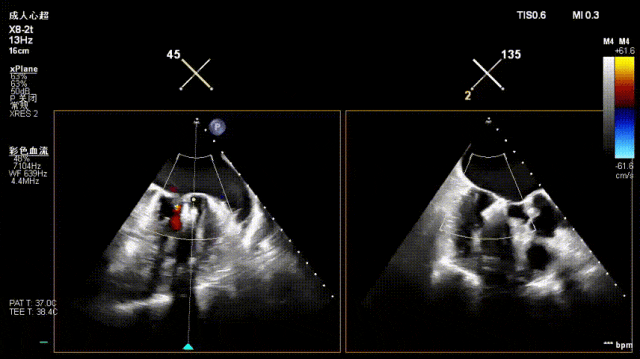

术前经食道超声显示:二尖瓣C1、P1区脱垂,重度关闭不全,彩色多普勒提示大量二尖瓣反流。术前瓣口面积MVA约5cm²,瓣环前后径AP约36.9mm,前叶A1约26mm,后叶P1约15.2mm。

患者全麻后仰卧位,常规消毒铺巾,置入下食道超声探头。于左前胸第五肋间做小切口,暴露心尖,全身肝素化后,心尖穿刺,逐步送入二尖瓣夹系统。术中在超声引导下,分别于C1及A1/P1区植入2枚ValveClamp®二型(MVC-Ⅱf)二尖瓣夹,夹合后超声显示二尖瓣反流明显减轻,随即释放夹子。术后置左侧胸腔引流管1根,逐层关闭胸壁,患者顺利转入ICU观察。

一夹后图像,残余反流位于2区

确认夹子位于反流区